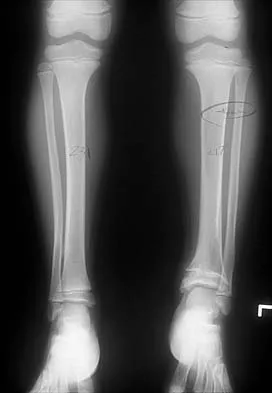

Question 50

A 13-year-old patient has foot drop and lateral knee pain. AP and lateral radiographs and an MRI scan are shown in Figures 49a through 49c. A biopsy specimen is shown in Figure 49d. What is the preferred method of treatment?

Explanation

The "sunburst" radiographic appearance suggests an osteosarcoma, and the histologic findings confirm the diagnosis with malignant cells surrounded by pink osteoid. MRI scans are not particularly helpful in the diagnosis of osteosarcoma but are mandatory for surgical planning. Osteosarcomas are high-grade sarcomas that are best treated with chemotherapy and wide resection. Even though the peroneal nerve is involved, limb salvage is indicated. Survival after limb salvage is equivalent to amputation, with better function. Goorin AM, Abelson HT, Frei E: Osteosarcoma: Fifteen years later. N Engl J Med 1985;313:1637. Link MP, Goorin AM, Miser AW, et al: The effect of adjuvant chemotherapy on relapse-free survival in patients with osteosarcoma of the extremity. N Engl J Med 1986;314:1600.